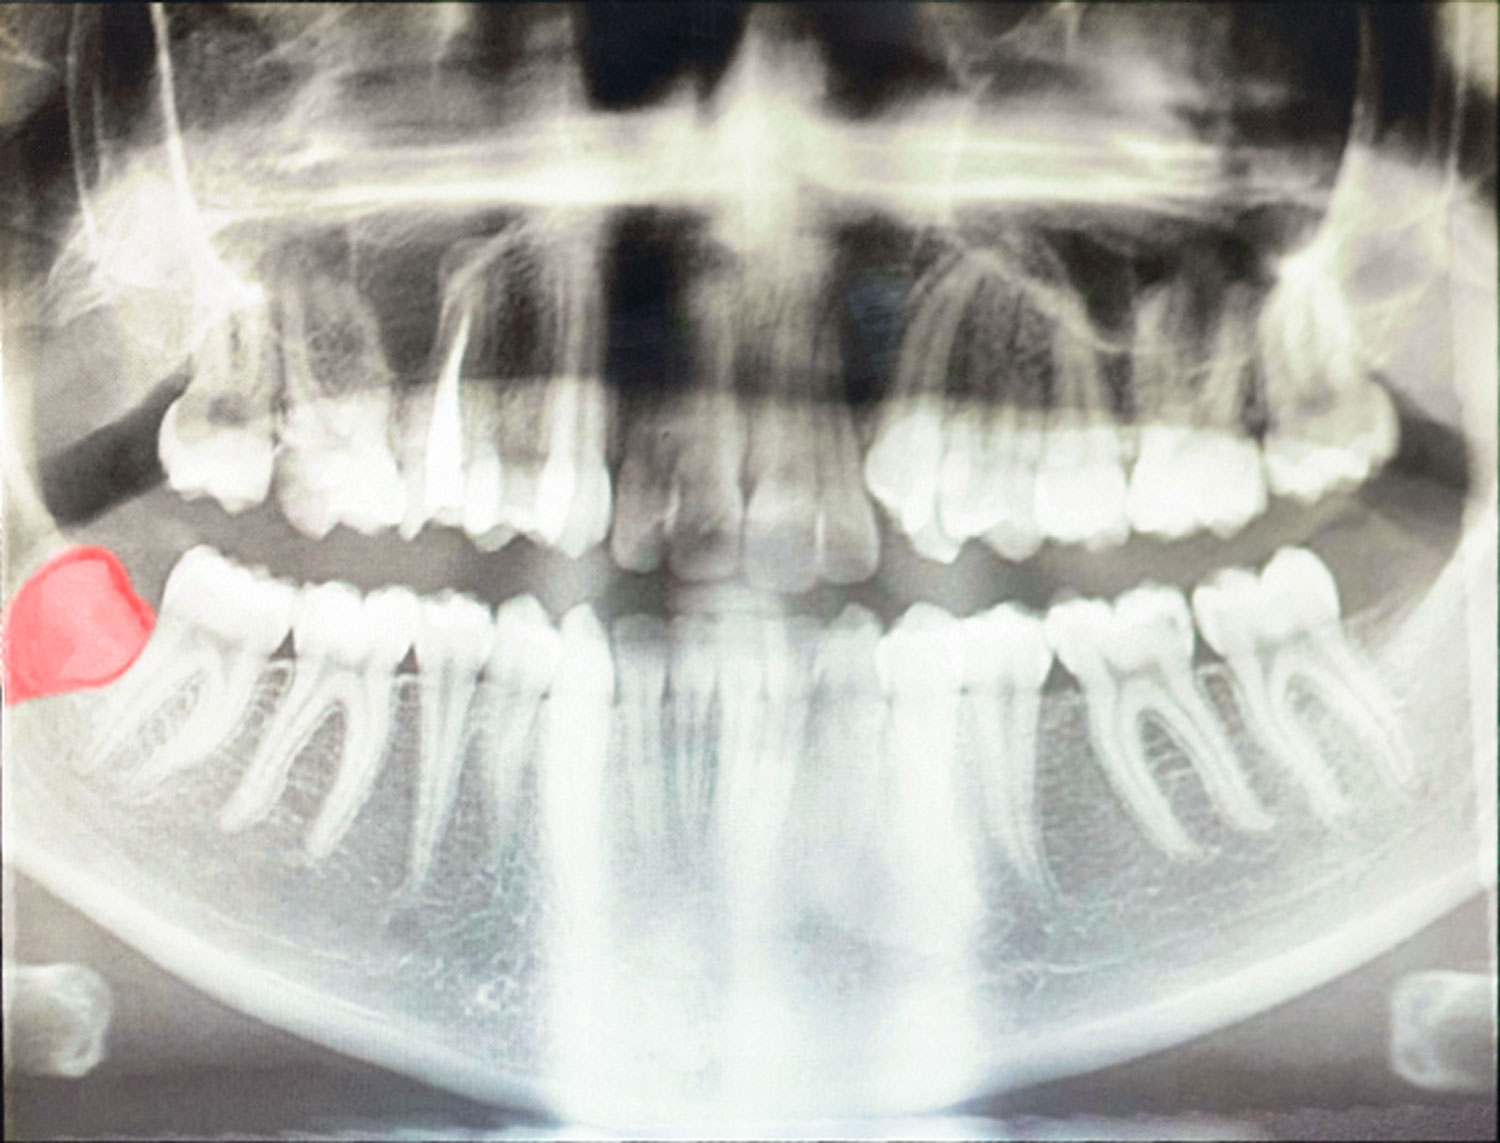

Oralchirurgie

Zur Oralchirurgie gehören alle chirurgischen Eingriffe im Mundraum. Die häufigste Behandlung ist dabei das Entfernen von Zähnen, insbesondere von Weisheitszähnen. Ebenso führen wir aber auch Wurzelspitzenresektionen durch, implantieren Zähne oder entfernen Zysten. Wir setzen dabei auf modernste Technik, sehen diese aber nur als Mittel zum Zweck: Am wichtigsten bleibt immer, dass Sie rasch wieder beschwerdefrei sind.